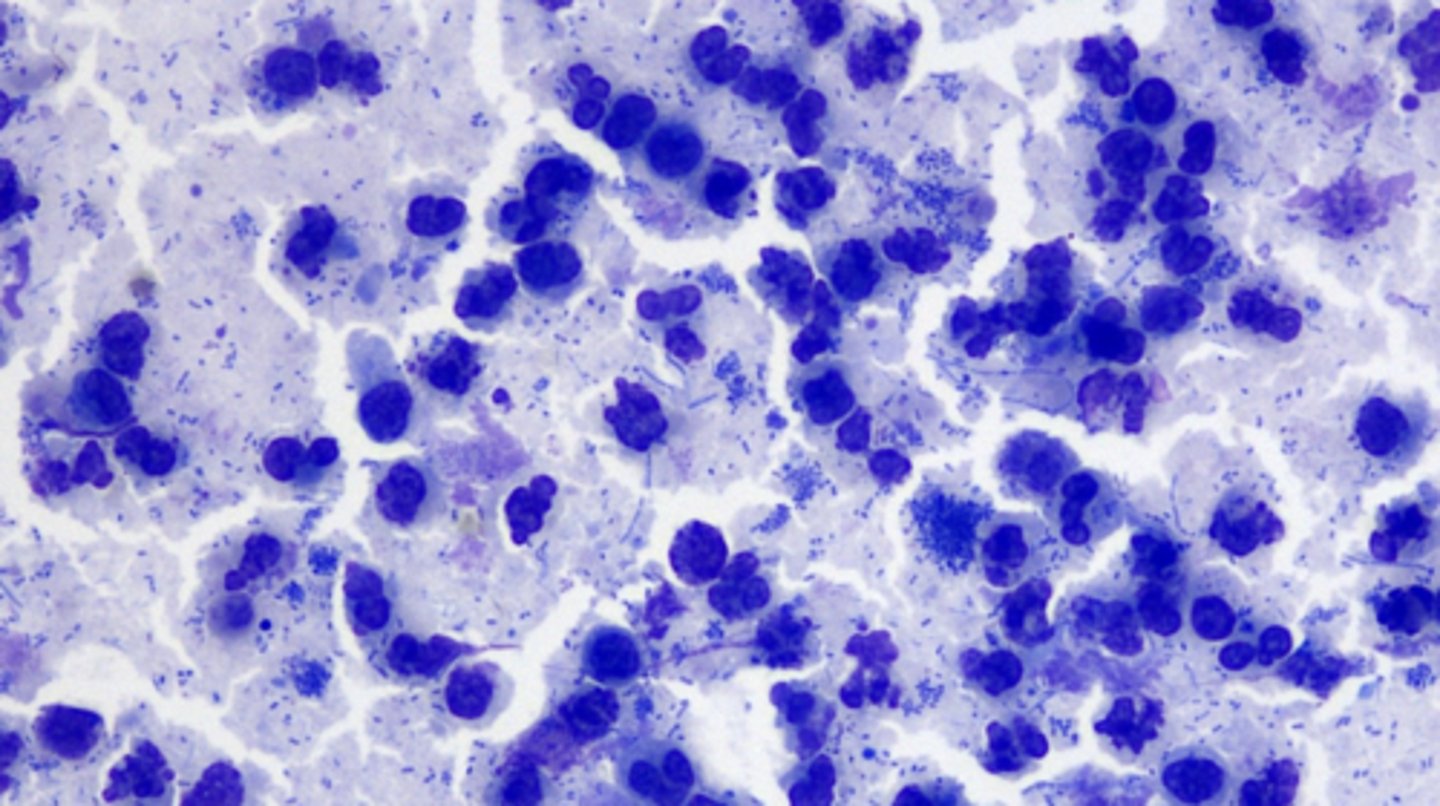

Boxer with generalized lymphadenopathy, what type of round cell tumor do you suspect?

Lymphoma

You aspirate a swollen lymph node and examine it under the microscope. What do you see?

Large lymphocytes

-LYMPHOMA

normal or abnormal?

abnormal

Large Cell Lymphoma

What malignancy characteristics are present?

What type of round cell tumor is this?